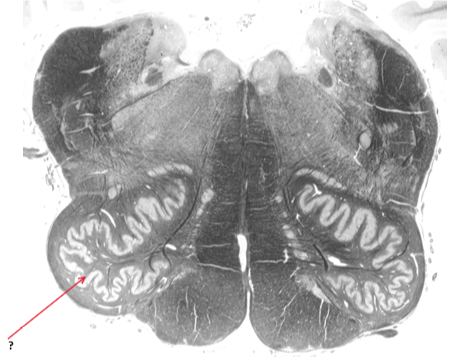

Name this and state its function.

Inferior olivary nucleus.